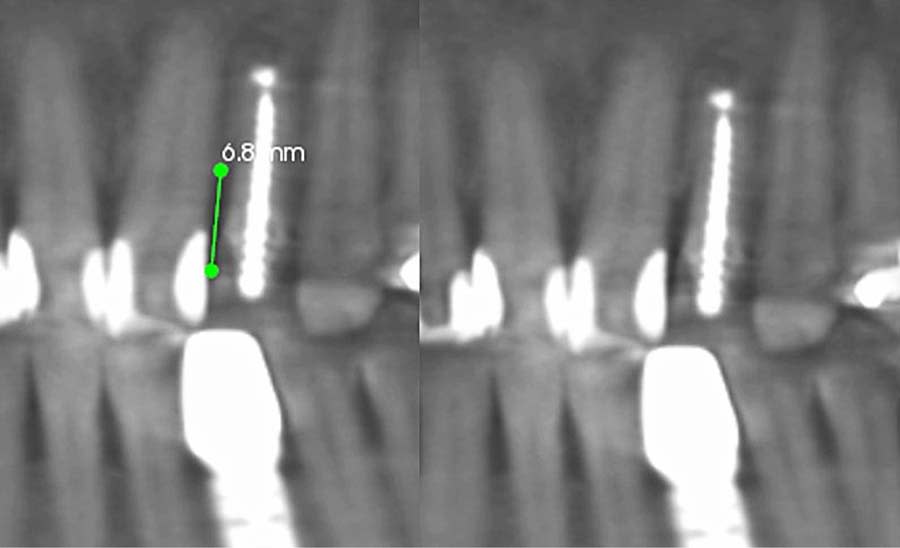

Dentofacial: The patient expressed concerns about mismatching tooth color, shape, and position. Her lip moved 10 mm from repose to Duchenne smile, placing her in the high end of normal range (6 mm to 10 mm).3 Gingival margins were uneven with supraeruption present resulting in a diagnosis of dentoalveolar extrusion with wear.4 Tooth rotations and overlaps were present as was a “black triangle,” ie, missing papilla, between teeth Nos. 9 and 10 due to the 6.8 mm distance between the crestal bone and contact point (Figure 7 and Figure 8).5 Pronounced negative buccal corridors were evident. Gingival tissue was displayed while smiling, giving the patient a high-risk dentofacial diagnosis.

Gingival margin leveling: Dentoalveolar extrusion and wear were addressed by intruding the maxillary anterior teeth, gingival margins were leveled relative to CEJs, and tooth No. 10 was extruded to coronally position tissue and bone (Figure 9). The latter also reduced the black triangle and maximized the predictability of the esthetics for a future pontic site, as tooth No. 10 had a guarded prognosis.7